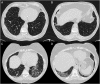

Rheumatoid arthritis (RA) is a systemic inflammatory disorder affecting approximately 1.3 million adults in the United States. Approximately 10% of these individuals with RA have clinically evident interstitial lung disease (RA-ILD), and an additional one-third demonstrate subclinical ILD on chest CT scan. The risk of death for individuals with RA-ILD is three times higher than for patients with RA without ILD, with a median survival after ILD diagnosis of only 2.6 years. Despite the high prevalence and mortality of RA-ILD, little is known about its molecular features and its natural history. At present, we lack a standard validated approach to the definition, diagnosis, risk stratification, and management of RA-ILD. In this perspective, we discuss the importance of clinical and translational research and how ongoing research efforts can address important gaps in our knowledge over the next few years. Furthermore, recommendations are made to design multicenter collaborative studies that will expedite the development of clinical trials designed to decrease the significant morbidity and mortality associated with RA-ILD.